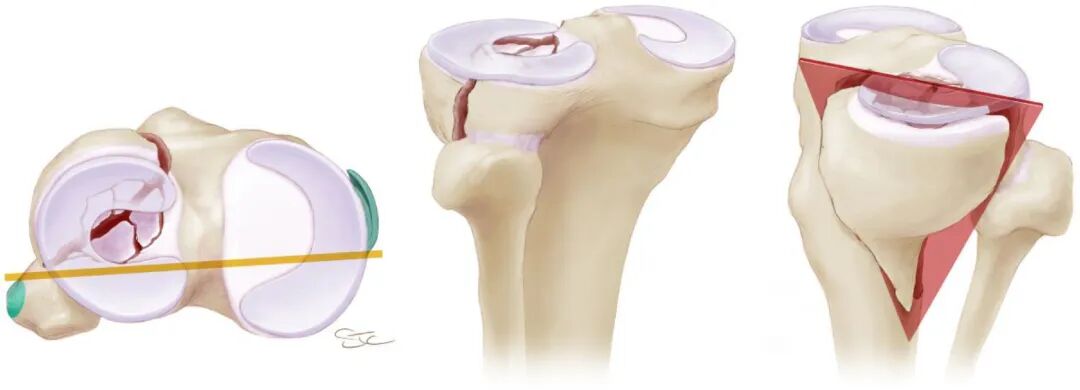

胫骨平台关节面不仅承担下肢负重和应力传导,还参与维持膝关节的正常活动度,关节面复位质量对膝关节功能的恢复十分重要。大多数学者倾向于复位后关节面台阶或分离不应超过2~4 mm。

胫骨平台关节面的复位要求还与骨折关节面所处区域有关,对于核心负重区[即膝关节在完成日常运动(如步行和中等强度跑步)过程中,胫骨平台的主要承重区域]的关节面骨折,应当力求手术解剖复位;而对于非核心负重区的骨折,则可适当放宽复位要求,甚至可采取保守治疗。